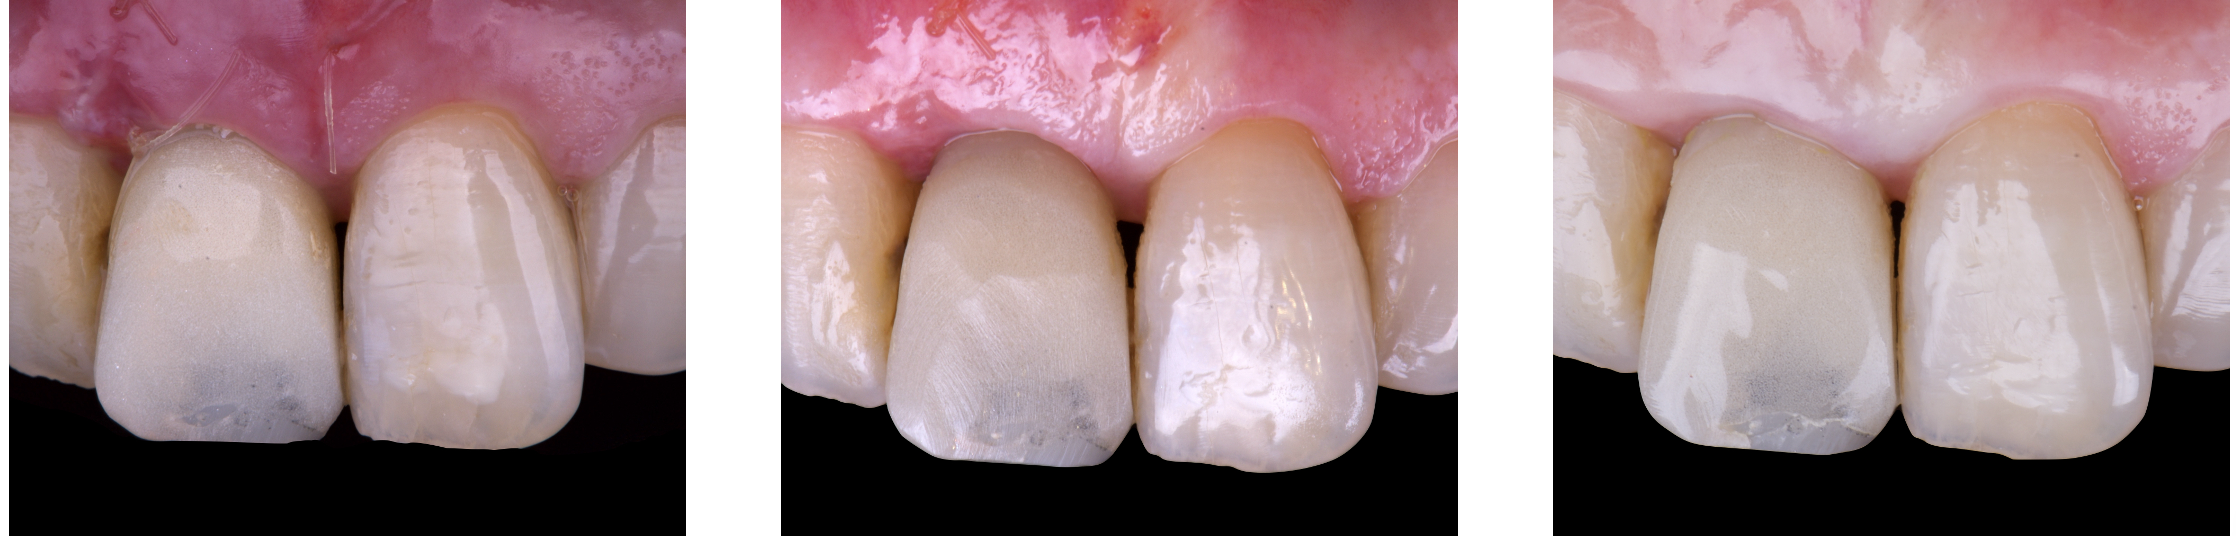

On the same day as the surgery, an immediate-load provisional crown was delivered. This restoration was fabricated in acrylic resin and screw-retained on the implant, following the “one abutment one time” principle. The provisional crown was carefully adjusted to avoid occlusal loading while supporting the peri-implant soft tissue architecture during the healing phase.

The provisional not only satisfied the patient’s functional and esthetic demands but also played a key role in shaping the emergence profile and conditioning the gingival margin. By providing a provisional solution immediately, the patient was able to leave the clinic with a natural-looking smile, avoiding any psychological or social impact associated with tooth loss in the anterior maxilla.